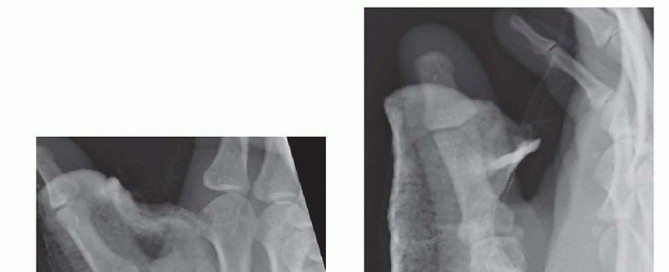

Our imaging protocol must be exhaustive to provide a three-dimensional understanding of the fracture morphology. Standard hand radiographs are insufficient due to the unique 30-degree pronated position of the thumb relative to the rest of the carpus. A True AP View of the Thumb CMC Joint (Robert's view) is obtained with maximal forearm pronation, placing the dorsum of the thumb flat on the cassette. This optimizes visualization of the joint space and the critical ulnar fragment. The True Lateral View (Billing and Gedda) is achieved with the hand pronated 20 degrees and the thumb flat on the cassette, with the X-ray beam tilted 10 degrees from vertical in a distal-to-proximal direction.

For complex, multi-fragmentary Rolando fractures, a Traction View under fluoroscopy is indispensable. Distraction at the CMC joint utilizes ligamentotaxis to help delineate comminuted fragments and assess the potential for closed reduction and percutaneous pinning versus the absolute need for open plating. Furthermore, when plain films inadequately delineate the spatial orientation of fracture fragments, particularly in Zone 2, a high-resolution Computed Tomography (CT) scan is strictly indicated. 3D reconstructions are invaluable for preoperative templating, allowing the surgeon to precisely map screw trajectories and select appropriate plate morphology before entering the operating theater.